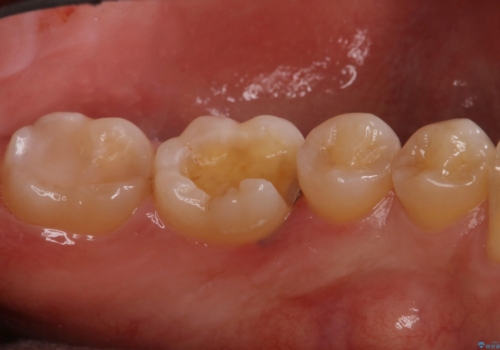

- 下の奥歯が黒いことが気になり来院された患者様です。

レントゲンなどから隣接面にも、う蝕があることが判明しました。

一部歯に保険治療で使用されている材料が劣化していたため、う蝕と一緒に取り除いて劣化の少ないセラミックに置き換わりました。